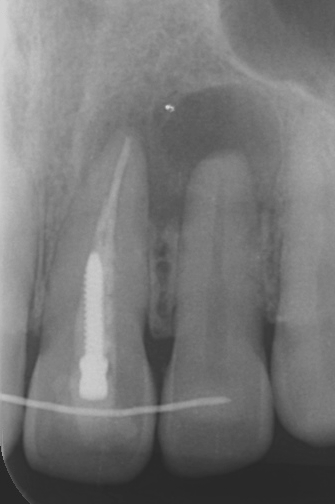

左上顎中切歯:抜歯即時埋入・即時負荷によるインプラント埋入、CTG(結合組織移植術)、セラミッククラウンによる上部構造

前歯は抜歯をすることで、歯根からの血流供給を受ける束状骨が必ず吸収し、唇側のボリュームが失われます。良好な審美性を維持するため、当院では陥没する歯肉を補うCTG(結合組織移植)を基本的にルーティンで行っています。

治療前後の写真です。ホワイトニングも行い、口腔内全体が明るい印象になりました。 レントゲンでは、右上顎中切歯の透過像は縮小しており、根尖性歯周炎は治癒傾向にあります。